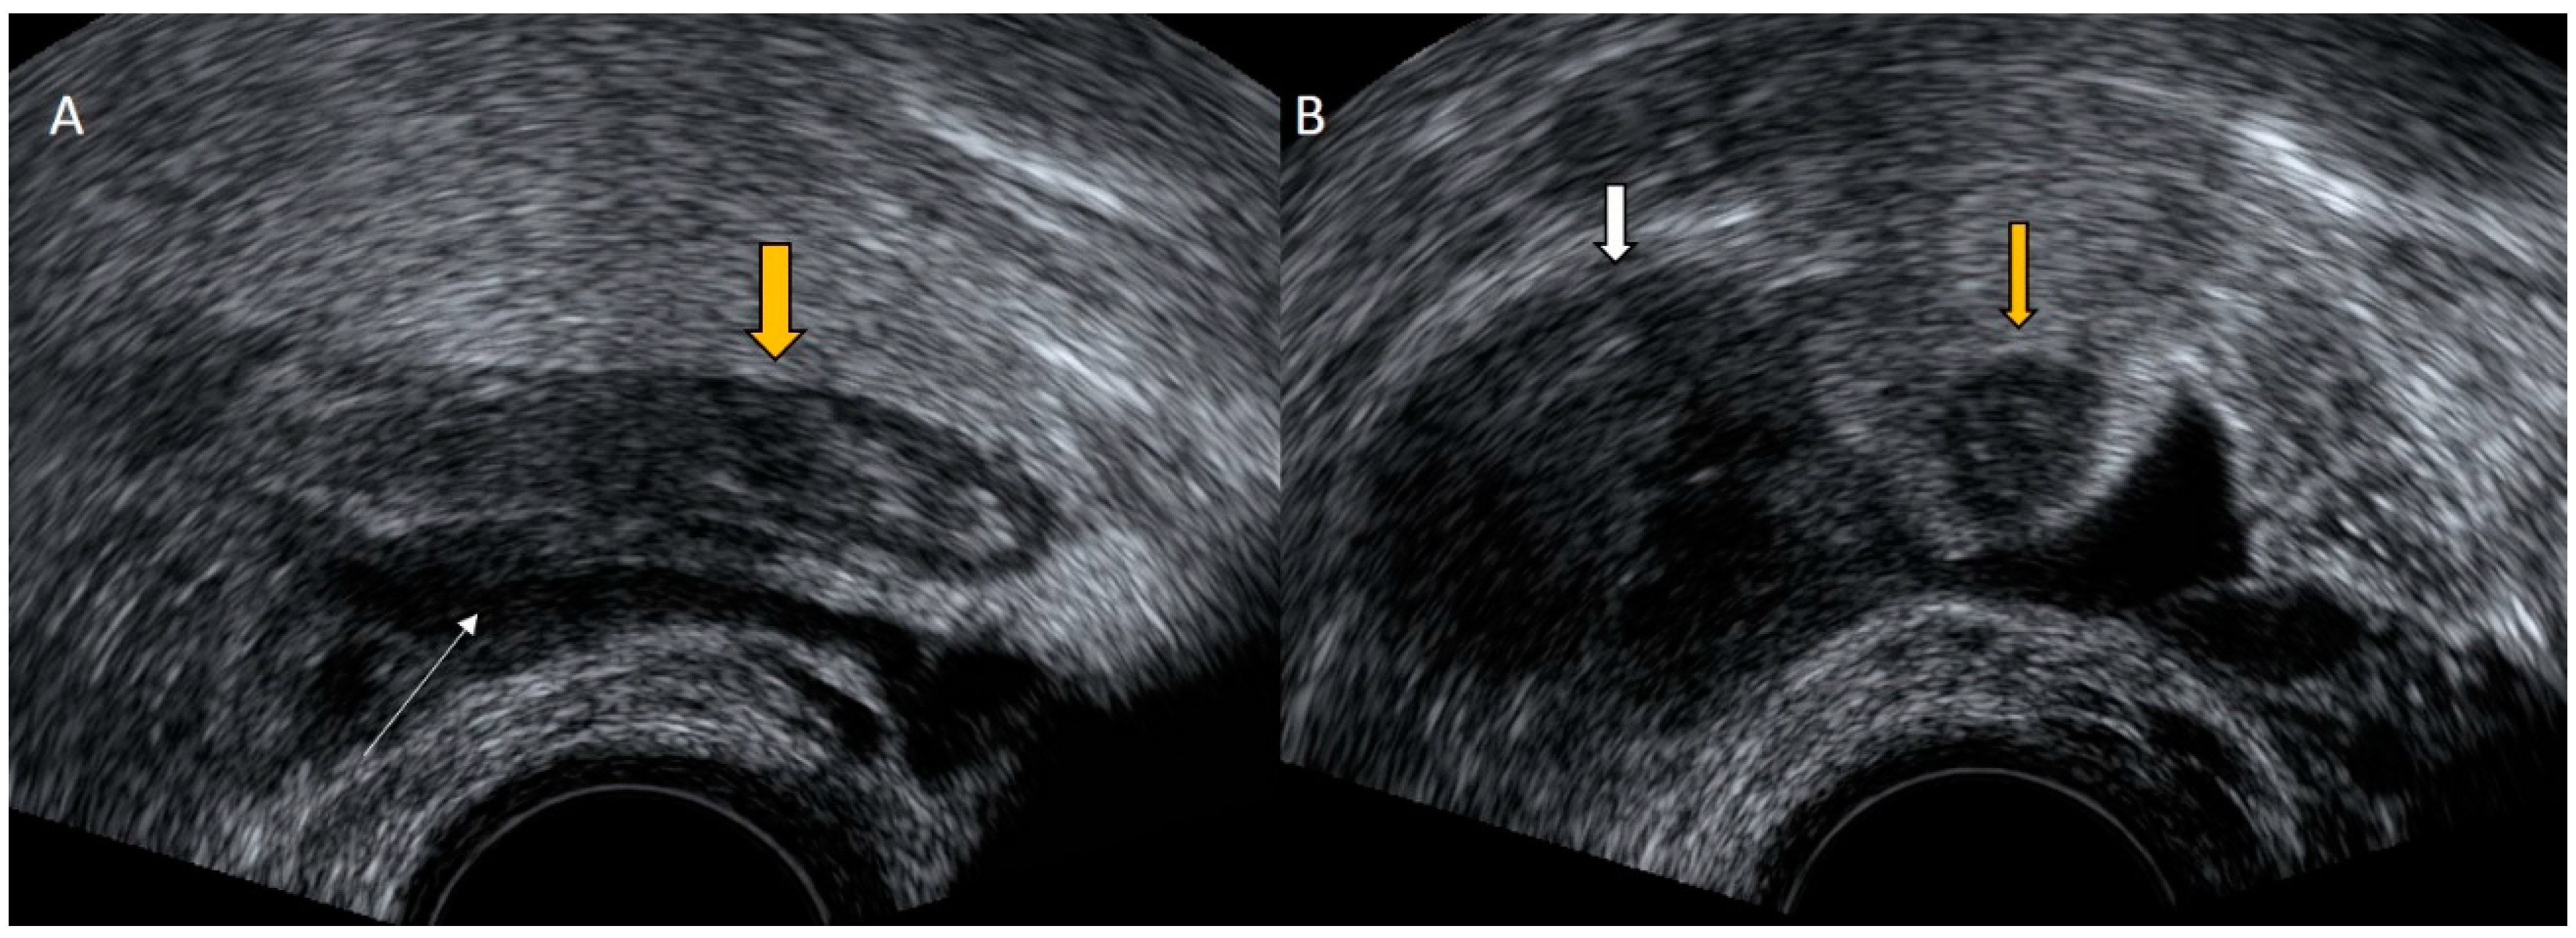

4.1. Pelvic Congestion